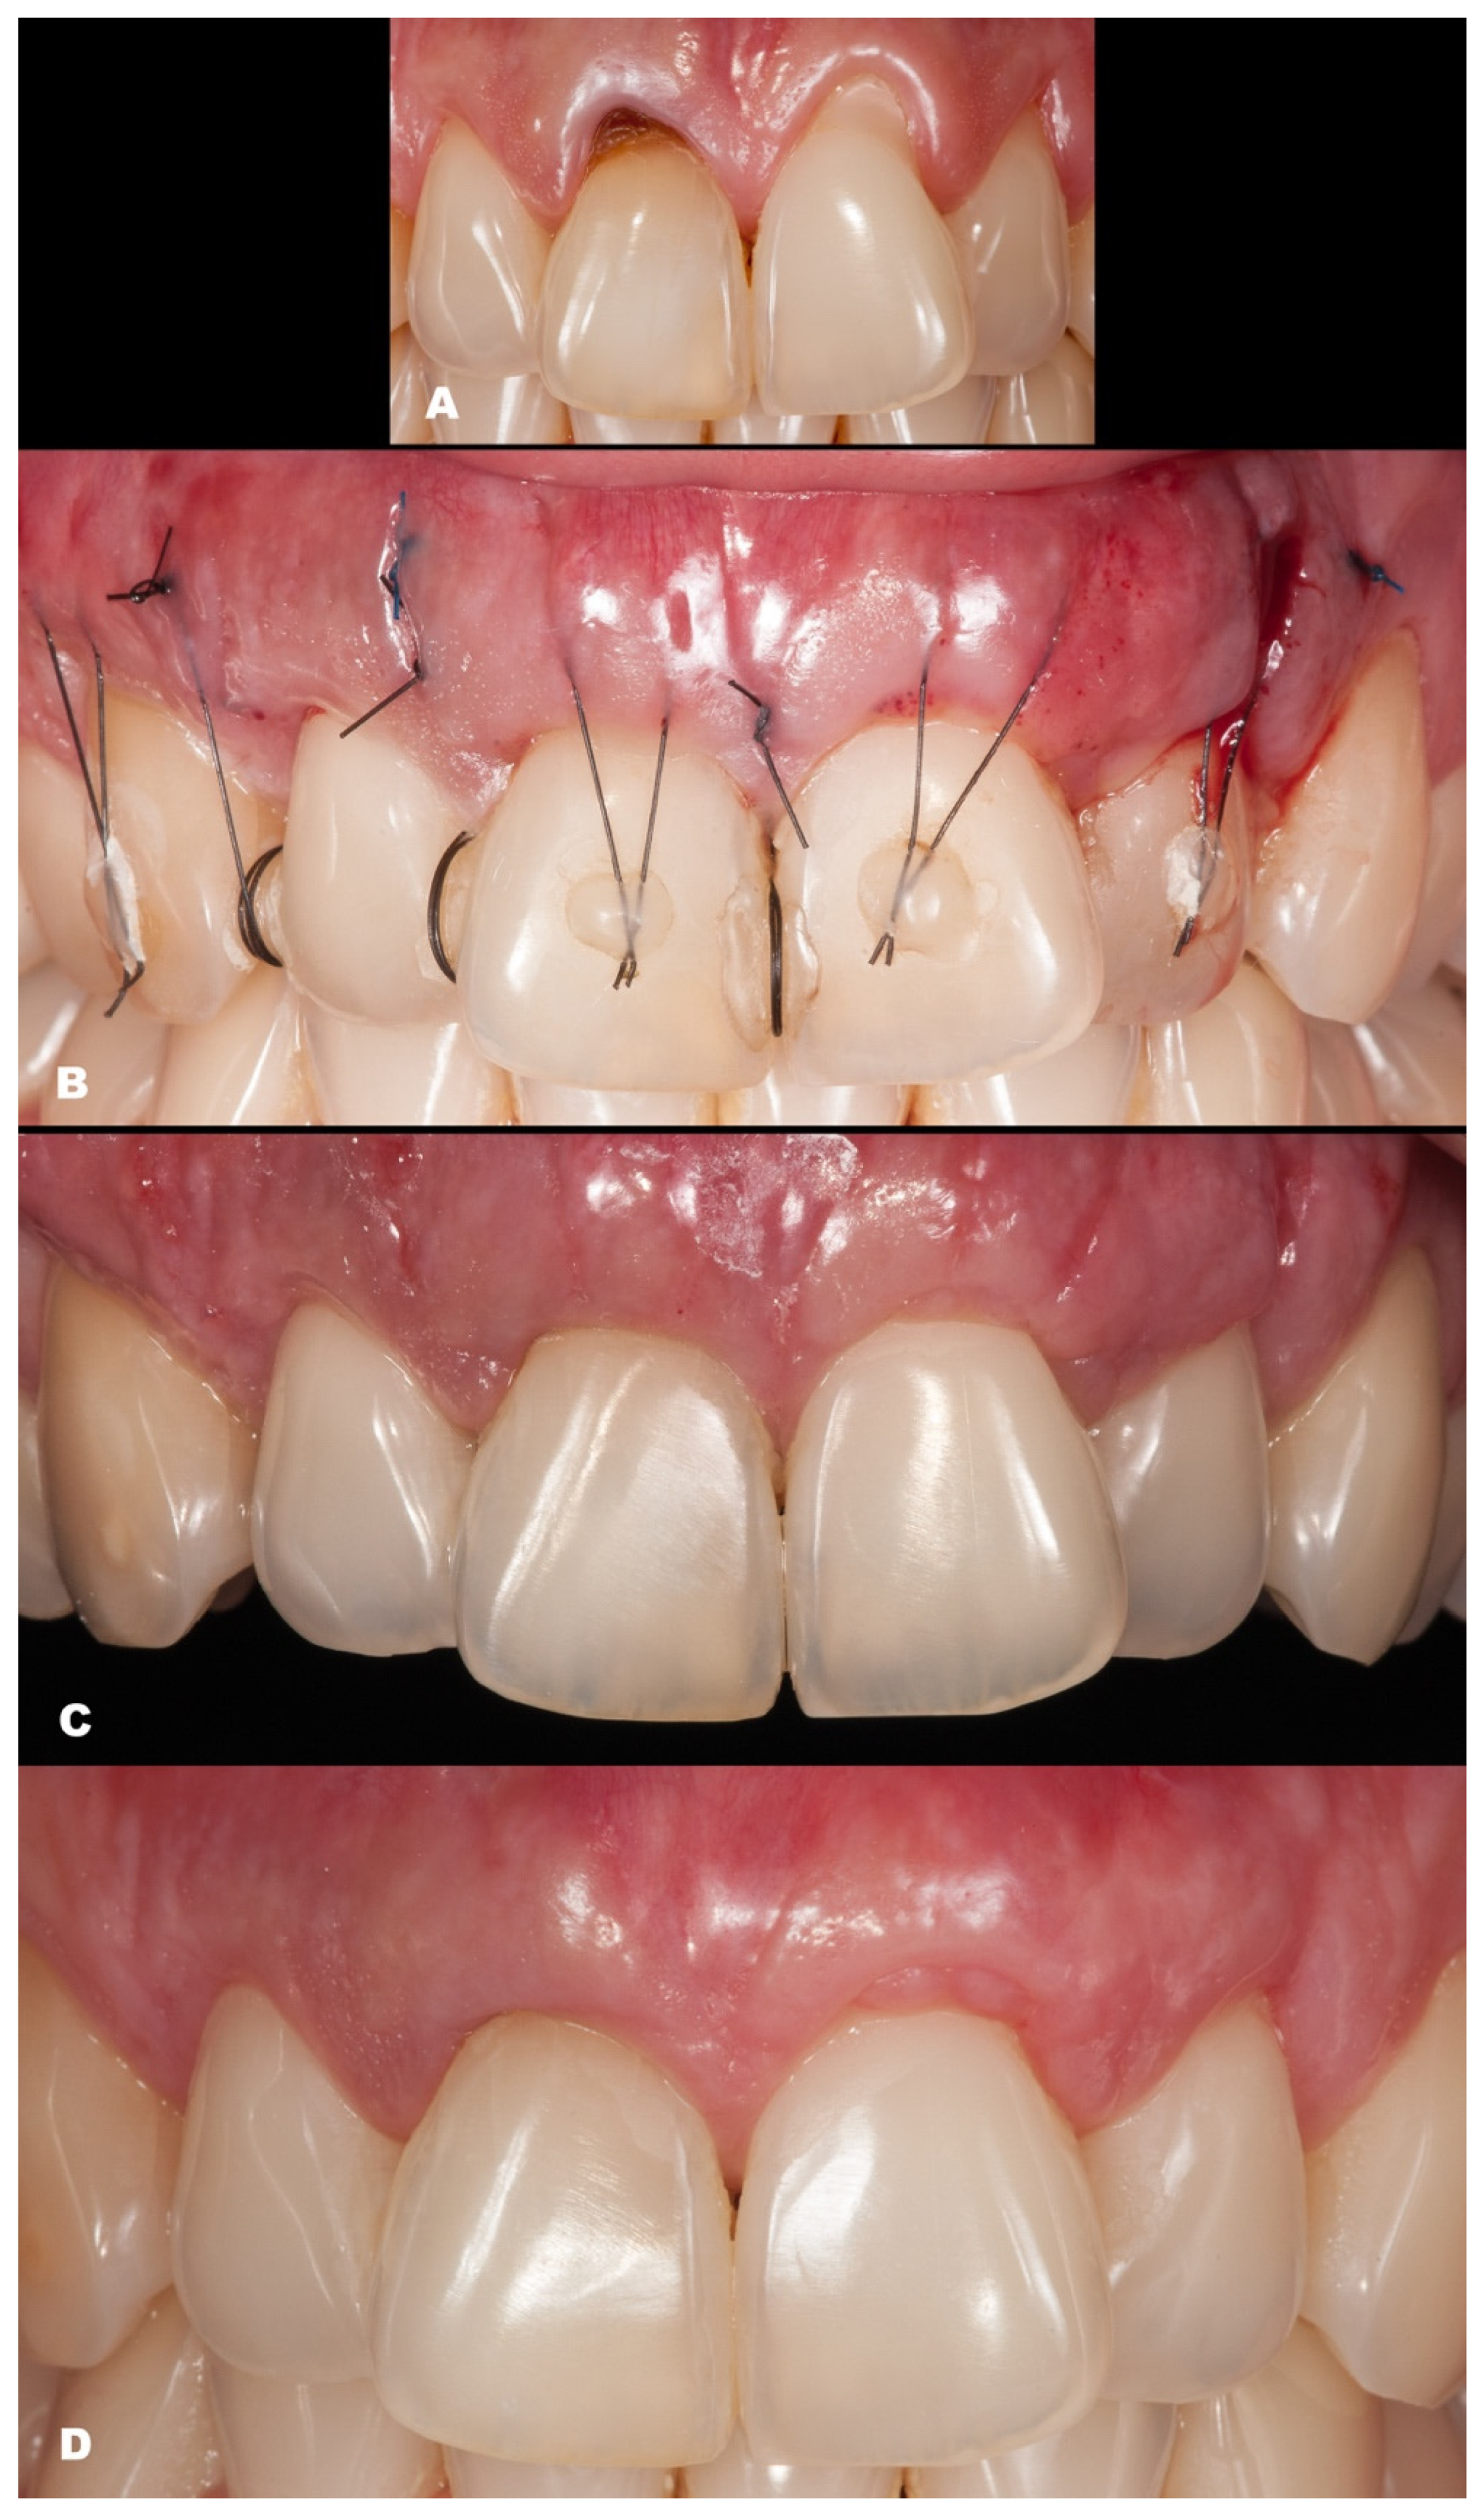

| Classification | Gender | Tooth/Teeth with REC | Initial REC Height (mm) | Initial REC Width (mm) | Initial PD (mm) | Initial KTW (mm) | Final REC Height (mm) | Final PD (mm) | Final KTW (mm) | % RC | p-Value | |

|---|---|---|---|---|---|---|---|---|---|---|---|---|

| Baseline | 6-Month Follow-up | |||||||||||

| Case 1 | RT2 | M | 41 | 6.2 | 2.5 | 1.0 | 0.3 | 1.1 | 2.0 | 4.3 | 82.25 | REC: p < 0.0001 PD: p = 0.2771 KTW: p = 0.1013 |

| Case 2 | RT1 | F | 31 | 3.3 | 1.7 | 0.5 | 0.3 | none | 1.0 | 3.7 | 100 | |

| Case 3 | RT1 | F | 41 | 1.2 | 2.1 | 1.0 | 3.3 | none | 0.5 | 7.3 | 100 | |

| Case 4 | RT1 | F | 41 31 | 1.4 1.2 | 2.1 1.8 | 1.0 0.5 | 3.1 2.9 | none | 1.0 0.5 | 3.7 4.0 | 100 100 | |

| Case 5 | RT1 | M | 43 | 1.5 | 2.3 | 1.0 | 1.3 | none | 1.5 | 4.4 | 100 | |

| Case 6 | RT1 | F | 43 44 45 | 1.2 2.1 1.4 | 2.6 3.1 2.8 | 2.0 1.5 1.0 | 3.0 3.8 3.8 | none | 1.5 1.0 1.0 | 2.1 2.8 5.3 | 100 100 100 | |

| Case 7 | RT1 | F | 12 11 21 22 | 1.1 1.5 2.4 1.5 | 1.5 3.0 4.0 2.0 | 1.0 2.0 1.5 2.0 | 5.4 5.0 6.3 6.9 | none | 1.0 2.5 2.5 1.5 | 4.3 5.7 6.0 6.3 | 100 100 100 100 | |

| Case 8 | RT2 | F | 42 41 31 32 | 2.2 3.4 3.2 1.2 | 2.3 2.5 3.0 2.7 | 0.5 0.5 0.5 1.0 | 2.4 1.9 1.5 3.5 | 0 0.6 0.6 0.5 | 1.5 1.0 1.0 1.0 | 3.6 2.9 2.1 3.3 | 100 82.35 81.25 58.34 | |

| Case 9 | RT1 | F | 12 13 | 1.3 2.1 | 2.2 2.3 | 1.5 2.0 | 4.4 5.3 | none | 2.5 1.5 | 4.6 5.2 | 100 100 | |